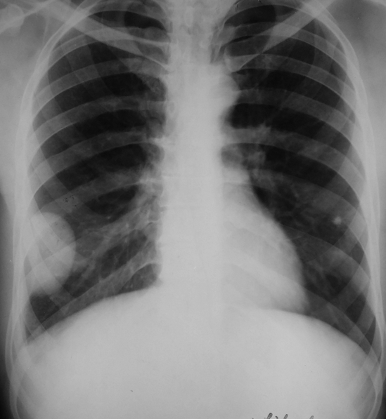

Rx toracică, incidență P-A

DESCRIERE: DAS + stază

indice cardiotoracic ↑

semne de dilatare a AS:

dublu contur inferior drept (contur dublu “festonat“)

deschiderea unghiului de bifurcație a traheei >120 grade

bombarea arcului mijl stg (golful pulm) → HTP

semne de stază pulm: dilatarea hilurilor + apicalizarea circulației + linii Kerley B

DX: stenoză mitrală

DD: insuf mitrală, boală mitrală, stenoză Ao